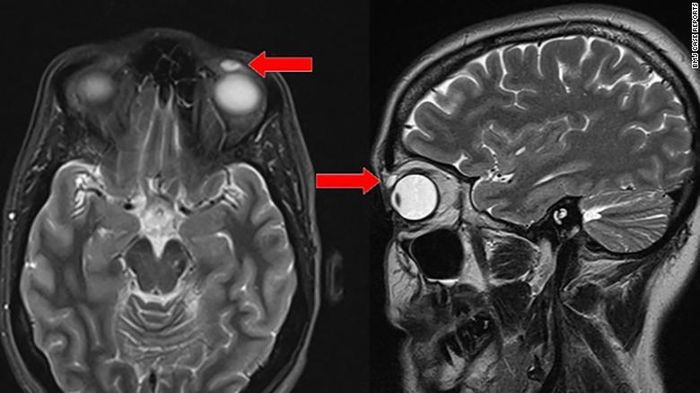

Namun saat diperiksa lebih lanjut, ahli bedah menemukan sebuah lensa kontak yang kaku terselip dalam kelopak mata wanita itu.

Saat ahli bedah menemukan lensa kontak itu, masih kaku dan utuh. Saat diangkat, barulah lensa itu retak dan terkelupas.

Kasusnya berbeda pada wanita ini karena menggunakan lensa kontak jenis kaku gas-permeabel yang dapat mentranmisikan oksigen. Lensa kontak itu seolah dienkapsulasi selama ini di dalam mata.